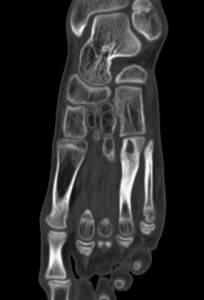

Спицевой канал был шире в области кортикальной пластинки. Плотность стенок спицевого канала увеличивалась до 480 [420;620] HU (медиана) (рис. 4, а). При локализации СО в дистальной трети большеберцовой кости и длительном течении заболевания (больше года) изменения в данной области проявлялись участками деструкции, нарушением структуры кости, появлением зон разрежения и склероза. Во всех случаях воспалительный и деструктивный процесс распространялся на кости стопы, сопровождаясь дефектами, изменением структуры с нарушением органотипического строения костей, зонами резорбции (рис. 4, б, в).

У больных с длительно текущим СО (более трех-четырех недели) или при рецидивах заболевания, рентгеноморфологическая картина деструктивных изменений кости в метафизарных отделах практически не отличалась от типичной для хронического остеомиелита. В частности, при локализации хронического остеомиелита в метафизарном отделе большеберцовой кости воспалительный и деструктивный процессы распространялись и на кости стопы. При этом мы отмечали изменения анатомии (дефекты, неровные контуры), снижение плотности костной ткани, а также зоны склероза и резорбции. Эти данные подтверждаются результатами ряда клинических и рентгенологических исследований [26, 27], что позволяет считать их достоверными и воспроизводимыми. При наличии хронической инфекции секвестр является основным диагностическим признаком хронического остеомиелита. Однако секвестры могут наблюдаться и при других заболеваниях, таких как эозинофильная гранулема, остеоид-остеома, где также описан так называемый «пуговчатый» секвестр [17, 18, 19]. Эти работы подробно описывают особенности «пуговчатого» секвестра и его клиническое значение, что важно учитывать при дифференциальной диагностике.

Ранние рентгенологические признаки спицевого остеомиелита включают расширение границ спи- цевого канала, усиление плотности его стенок, нечёткость контуров и формирование линейного или гребневидного периостита вокруг спицы. В метафизарных отделах спицевые каналы характеризуются повышенной плотностью стенок (200-400 HU), низкой плотностью содержимого, включая участки с отрицательными значениями по шкале Хаунсфилда (HU), а также чёткими демаркационными зонами, что отражает наличие воспалительного процесса с формированием границ между поражённой и здоровой тканью. В диафизарных отделах каналы шире, стенки имеют неровные контуры и плотность, сопоставимую с кортикальной пластинкой (500-700 HU), что требует дифференциальной диагностики с другими заболеваниями, такими как опухолевые процессы или доброкачественные опухоли кости.

Секвестры при СО демонстрируют выраженную вариабельность в зависимости от локализации: в метафизарных отделах секвестры обладают плотностью вдвое меньшей, чем в диафизе (250-350 HU против 600-700 HU), меньшими размерами и неправильной формой. В диафизе типичны «замурованные» секвестры в кортикальном слое, а также фрагменты с плотностью до 800 HU, окружённые демаркационной зоной с плотностью 100-150 HU. Патогномоничным признаком длительно текущего (более трех-четырех недель) СО в области диафиза является секвестр, повторяющий контур спицевого канала, так называемый «кольцевидный» или «пуговчатый» секвестр, что подтверждает связь формирования секвестра с зоной проведённой спицы.